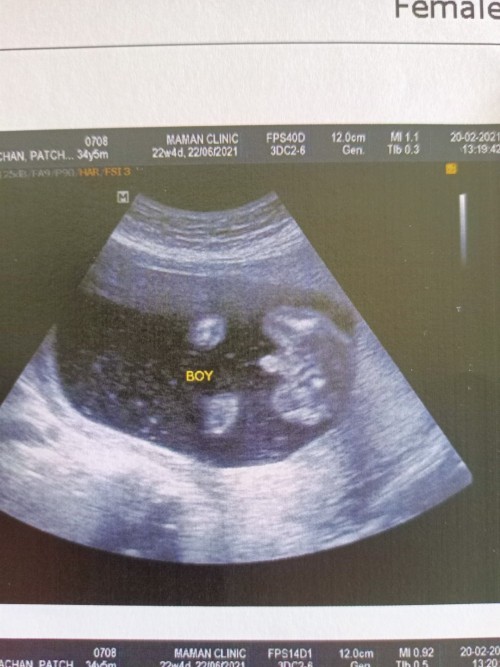

ชายค่ะ

ผช.ค่ะ